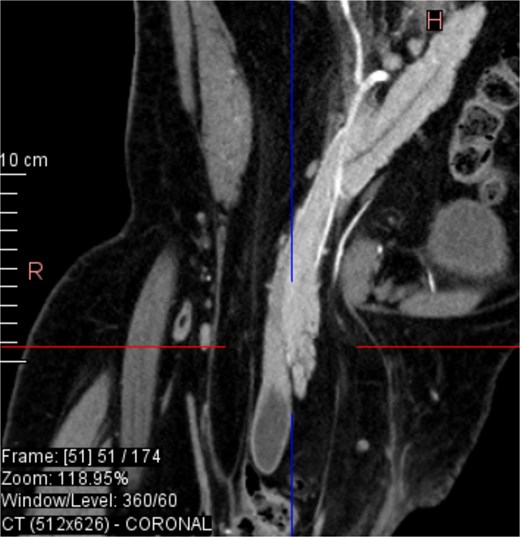

CT imaging (Figs 2–5) revealed a right inguinal hernia containing small bowel loops, ascending colon, the second and third portions of the duodenum, and the pancreatic head. The pancreatic head appeared rotated and displaced inferiorly into the hernia sac, without signs of acute pancreatitis.

Coronal CT view visualization of vascularization of pancreatic head after i.v. contrast.